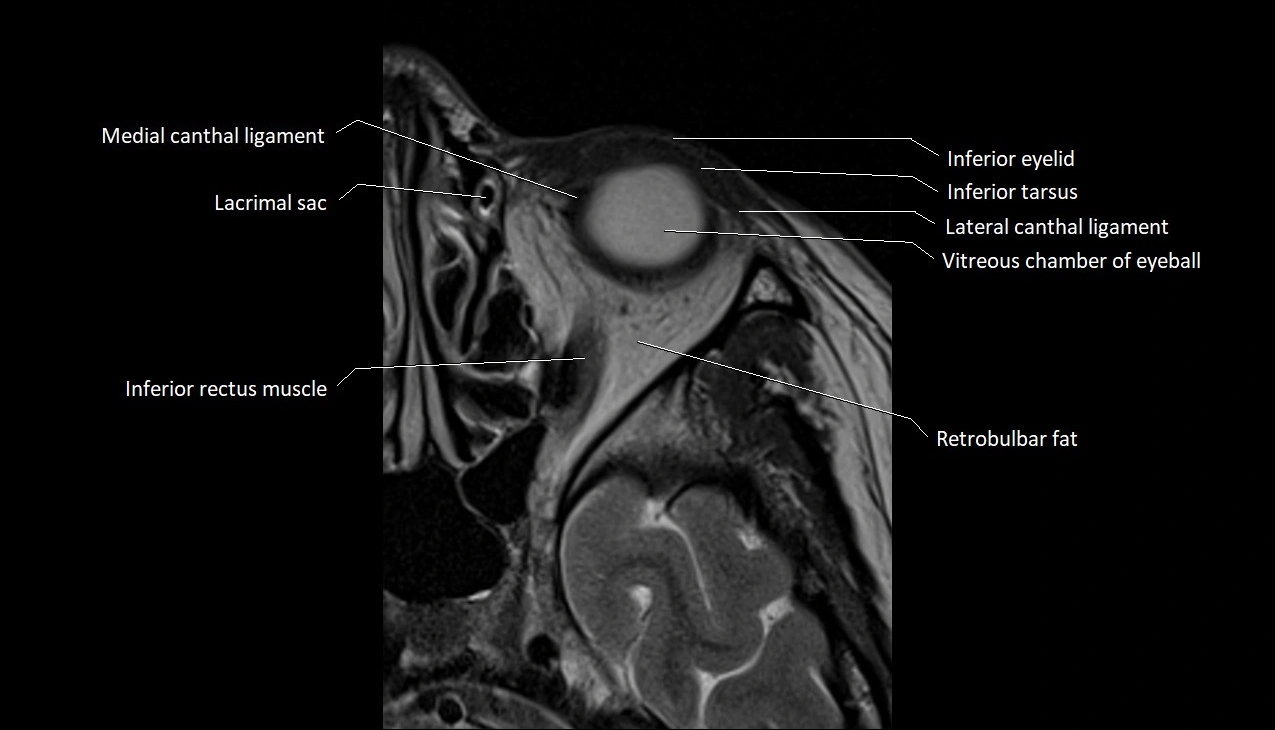

- Inferior eyelid

- Inferior rectus muscle

- Inferior tarsus

- Lateral canthal ligament

- Medial canthal ligament

- Retrobulbar fat

- Vitreous chamber of eyeball